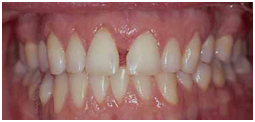

A UB orthodontist has documented that "playing" with a pierced-tongue stud can eventually result in a gap between the front teeth.

In many cases, patients did not have a space between their front teeth prior to the tongue piercing.

Subjects frequently develop a habit of pushing the metal stud in their tongues up against and between the front teeth, creating a gap.

Thousands of dollars of orthodontia may be required to close the gap, as was the case with this patient.

The study involved a 26- year-old female patient examined at UB's orthodontic clinic who complained that a large space had developed between her upper central incisors or upper front teeth. The patient also had a tongue piercing that held a barbell-shaped tongue stud.

The tongue was pierced seven years earlier and every day for seven years she had pushed the stud between her upper front teeth, creating the space between them and, subsequently, habitually placing it in the space. The patient did not have a space between her upper front teeth prior to the tongue piercing.

Her treatment involved a fixed braces appliance to push the front teeth back together.